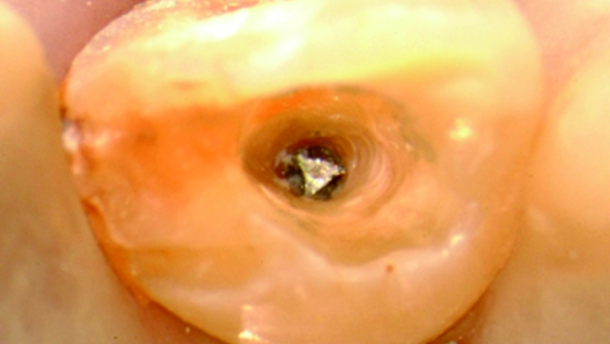

L’objectif du retraitement est d’éliminer les obstacles qui rendent difficile la mise en forme complète, le nettoyage et le remplissage du système canalaire. Grâce aux inserts ultrasonores et aux instruments rotatifs dédiés, nettoyer le système canalaire est beaucoup plus facile, plus rapide et plus sûr qu’il ne l’a jamais été.

L’endodontie a également fait un bon en avant depuis l’introduction du microscope opératoire. Une meilleure vision du champ opératoire permet la suppression en toute sécurité des bris d’instruments, de franchir des butées et la résolution des perforations.